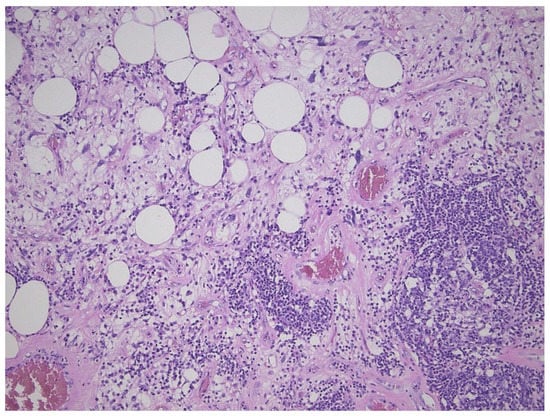

This tumor represents the most common malignant adipocytic neoplasm and is mainly seen in middle-aged adults. The deep soft tissues of the extremities are most frequently involved (75%), followed by the retroperitoneum (20%). The groin, paratesticulum and mediastinum are also known locations. The overall mortality is zero for lesions of the extremities and more than 80% for exactly the same tumors in the retroperitoneum. Therefore, the term “atypical lipomatous tumor” is used for lesions in surgically amenable sites where excision can be curative, like the extremities, and “well differentiated liposarcoma” for tumors presenting in the retroperitoneum, spermatic cord and mediastinum, where complete removal is often not possible leading to high morbidity and mortality. Three morphological subtypes are classically described: lipoma-like, sclerosing and inflammatory []. In the lipoma-like variant, the basic morphological hallmark is the presence of variation in adipocyte diameter, hyperchromatic/atypical nuclei and lipoblasts (Figure 1). In the sclerosing variant, scattered bizarre hyperchromatic cells and lipoblasts are seen in an extensive fibrillary stroma, varying from dens to myxoid (Figure 2). This subtype is most often seen in the retroperitoneum or paratesticular area. In the inflammatory variant, mainly seen in the retroperitoneum, a lymphoplasmocytic inflammatory infiltrate predominates and obscures the adipocytic component, to the extent that it can mimic inflammatory myofibroblastic tumor, Castleman’s disease or even a lymphoma (Figure 3). These phenotypic variants can be admixed in the same tumor. Whatever it looks like, WDL/ATL is characterized by giant marker and/or supernumerary ring chromosomes, both of which contain multiple copies of MDM2. This amplification results in nuclear MDM2 protein overexpression. There is frequently co-amplification of other genes of the 12q14-15 region, like CDK4, GLI1 and HMGA2, but MDM2 amplification is the main driver (Figure 4). Immunohistochemistry and/or FISH for MDM2 is frequently used to support the diagnosis of WDL/ATL, FISH being much more sensitive and specific than protein detection (Figure 5) [,]. MDM2 RNA ISH seems to be as performant as DNA FISH []. An important pitfall is the presence of nuclear MDM2 immunoreactivity in histiocytes/lipophages which are very often seen in traumatized fatty tumors. In addition, any cytoplasmic positivity is not diagnostic. The pathologist is often faced with lesions in which the histological changes are not convincing enough for WDL/ATL and thus, the differential diagnosis with an ordinary lipoma cannot be made on morphological grounds alone. This does not mean that every lipoma should be FISHed for MDM2, the following features justify the use of this test: (1) recurrent lesion, (2) deep extremity lesion larger than 10 cm in a patient over 50 years of age, (3) lesion with equivocal atypia, (4) lesion in the retroperitoneum/pelvis/abdomen, and (5) lesions not fitting the above criteria but having worrisome clinical or radiological features [].

Figure 3.

Inflammatory variant of well-differentiated liposarcoma/atypical lipomatous tumor, dominated by a prominent lymphoplasmocytic infiltration. Note the atypical fat cells as well.